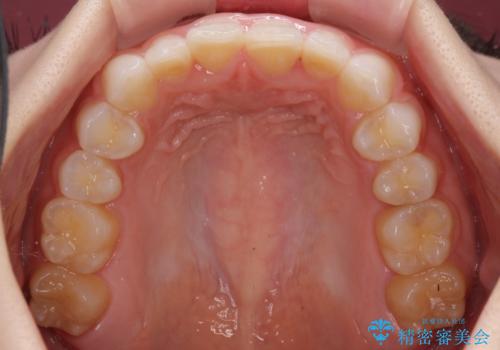

デコボコと深い咬み合わせの改善 インビザラインによる矯正治療

- 口元のデコボコと深い咬み合わせ(ディープバイト)を気にして来院された患者様です。

インビザラインによる上下歯列の拡大と、IPR(歯と歯の間を削る)にるスペースの獲得により、口元のデコボコとディープバイトを改善することとしました。